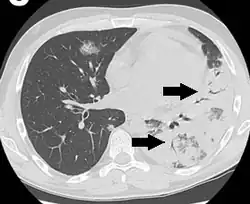

An air bronchogram is defined as a pattern of air-filled bronchi on a background of airless lung.[1]

In pulmonary consolidations and infiltrates, air bronchograms are most commonly caused by pneumonia or pulmonary edema (especially with alveolar edema).[2][3]

Other potential causes of consolidations or infiltrates with air bronchograms are:[2]